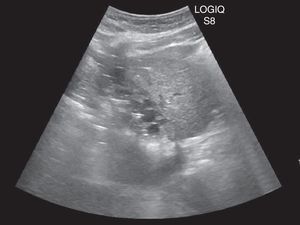

Varón de 70 años con antecedente de hidatidosis duodenal intervenida hace 30 años, que consulta por tumoración dolorosa en cicatriz de laparotomía. Durante una cura se abre espontáneamente y supura material seroso e hidátides. Una ecografía y una TC abdominal revelan una colección de contenido hipodenso en segmento hepático V, fistulizada a piel (figs. 1 y 2). Se explora quirúrgicamente la herida y se coloca drenaje multiperforado (fig. 3, flechas: hidatides). Se administra albendazol y se realizan lavados con suero salino hipertónico durante 2 semanas hasta la resolución clínico-radiológica del cuadro. El estudio microbiológico fue negativo y la anatomía patológica confirmó el diagnóstico de hidatidosis.